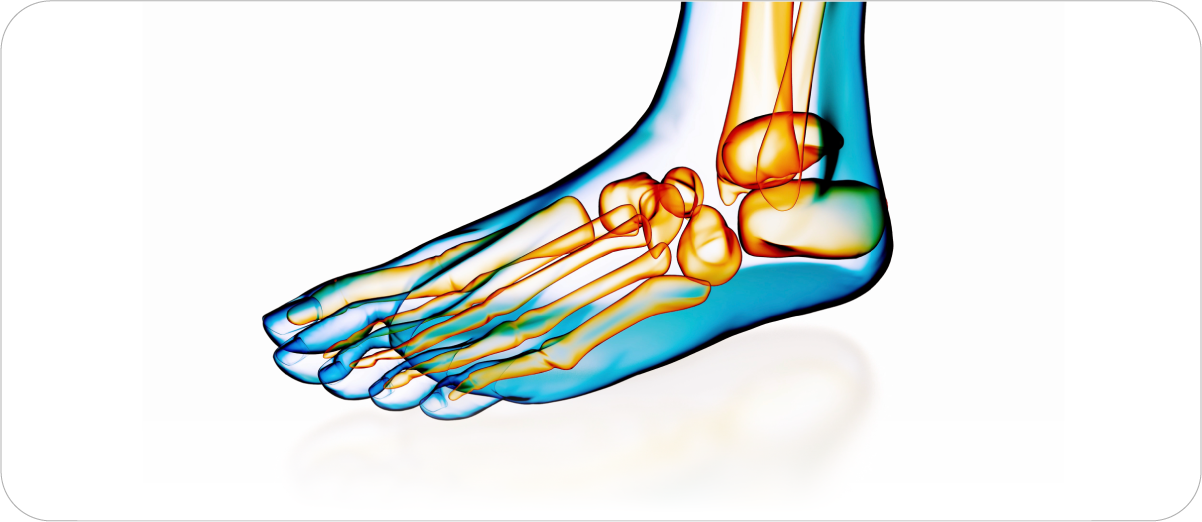

특허청 특허 등록 완료

국제첨단신발기능경진대회 1등 수상